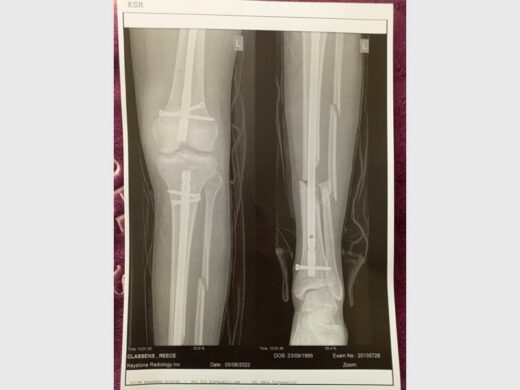

Once the wounds were more manageable he was taken to an orthopaedic surgeon for a check-up, who requested X-rays and a bone swab test. “It was the first time we saw an X-ray of his injured leg. His femur was angulated but touching, his tibula was not touching, and his fibula still had two breaks. His bone swab test came back positive for infection,” explained Verona.